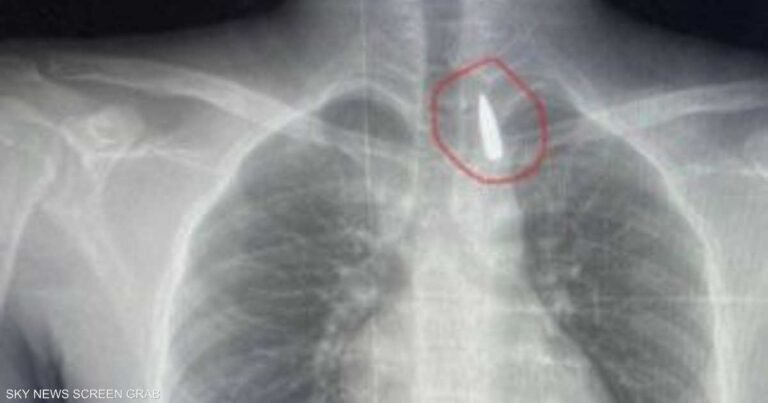

مقذوف استقر في صدره.. إنقاذ حياة مصاب من غزة في مصر مقذوف استقر في صدره.. إنقاذ حياة مصاب من غزة في مصر العراق الآن أكتوبر 25, 2025